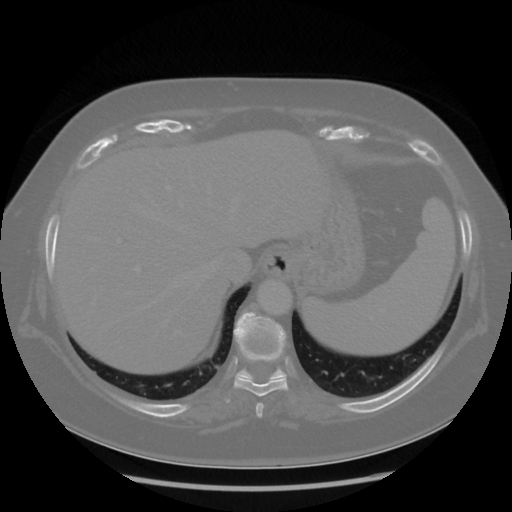

Original NATIVE CT scan (input)

Full window (WL 1023.5, WW 4095 β†’ Low βˆ’1024, High +3071)

Actual HU range: [-1024.0, 1077.0]